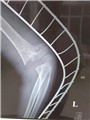

Trong gãy xương có nhiều phương pháp xử trí như phẫu thuật kết hợp xương, bó bột cố định, đai, nẹp…